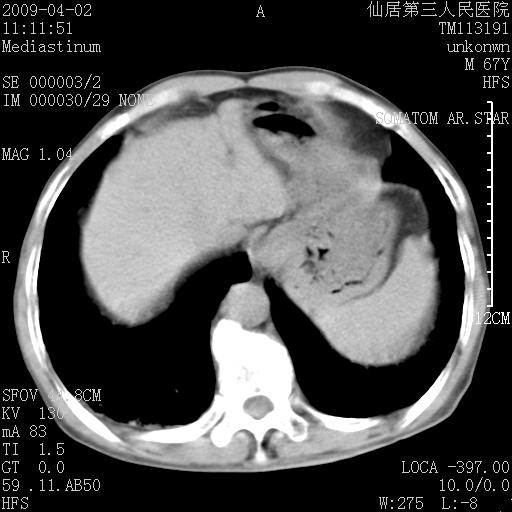

患者老年男性,乏力畏寒来诊,摄胸片示右下肺感染性病变,抗炎两周后复查胸片,无好转有进展。

后做ct平扫表现如下:

病灶呈蜂窝征,纵隔多个淋巴结肿大;肺泡癌需考虑

我认为普通的感染应该可以除外,间质性肺炎可能性较大,但如何解释纵膈的淋巴结肿大呢

考虑双肺间质性改变(间质纤维化?)伴右肺下叶感染。